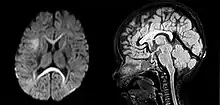

| An MRI of a patient with benign familial macrocephaly (male with head circumference > 60 cm) | |

Macrocephaly is a condition in which circumference of the human head is abnormally large.[1] It may be pathological or harmless, and can be a familial genetic characteristic. People diagnosed with macrocephaly will receive further medical tests to determine whether the syndrome is accompanied by particular disorders. Those with benign or familial macrocephaly are considered to have megalencephaly.